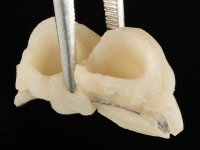

Foi feito o tratamento endodôntico dos dentes 2.1 e 2.2.de imediato, a sintomatologia que o paciente manifestava a isso impunha. Na mesma consulta foi realizada uma extensa gengivetomia com o bisturi elétrico, no sentido de expor os limites cervicais da fratura. Foram colocadas resinas compostas nos remanescentes radiculares com a intenção de reformular a emergência dos tecidos moles. Realizei a impressão dos remanescentes radiculares para confeção em laboratório de uma ponte provisória. A ponte provisória de 2 elementos, apresentava um formato que visava no futuro acomodar o coto dos espigões falsos cotos que iria ser cimentados nos remanescentes radiculares. Apresentava um reforço metálico palatino e dois apoios para os dentes adjacentes, um mesial e outro distal. Os remanescentes radiculares foram preparados para a confeção de dois espigões falso coto fundidos. As linhas de acabamento cervical foram definidas e os canais radiculares desobturados e preparados. A impressão foi realizada com a utilização de tutores de plástico com a técnica de dupla mistura. O afastamento gengival foi feito utilizando pasta de caolino. A ponte provisória foi rebasada em boca com acrílico auto polimerizavel, cimentada provisoriamente sobre as raízes e os apoios colados aos dentes adjacentes. No laboratório foram confecionados os E.F.C. fundidos, tendo o cuidado de preservar espaço para a definição no re preparo dentário da linha de acabamento cervical. Removida a ponte provisória foi feita a cimentação dos E.F.C. fundidos com cimento de ionómero de vidro reforçado com resina. A ponte provisória teve que ser retocada para permitir a acomodação dos cotos e simultaneamente foi readaptada à redefinida linha de acabamento cervical. Durante 2 meses a ponte provisória acompanhou a estabilização periodontal das raízes traumatizadas e simultaneamente conseguiu a maturação da arquitetura gengival.